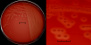

Small (approximately 1 mm in diameter) transluscent colonies after incubation for 24 h at 37°C. Many (but not all) strains give a (clear) zone of beta-hemolysis on blood agar. The hemolysis zone can be very thin or broad.